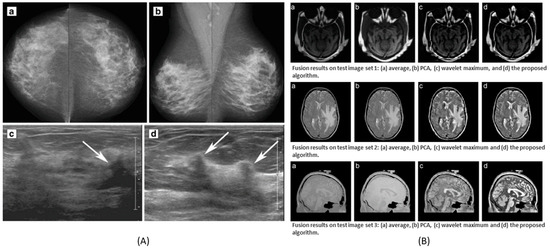

The combination of multivariate data of the second order of dimensionality (e.g., image data) can be seen from Figure 4A. Different types of medical images of human cells and organs indicate different kinds of details and features. Several combinations, e.g., ultrasound with mammogram, CT with MRI, and many more combinations perform well operating on different fusion levels, such as pixel-level, feature-level, and decision-level data fusion. Examples of some combinations can be seen in Figure 6.

Figure 6.

Data fusion as a result of different types of images. (A) Ultrasound and mammogram image fusion to detect breast cancer. (B) CT and MRI image fusion to provide high spatial quality of anatomical information and functional details of the diseases. (A) is reprinted with permissions from reference [36]. (B) is adapted with permissions from reference [37], 2008, Elsevier.